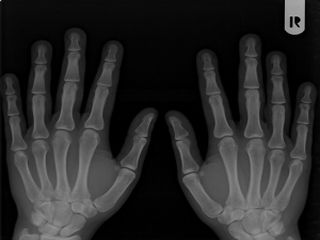

Sensibilitatea degetului uman

Degetul uman este atat de sensibil, incat, daca acesta ar avea marimea Pamantului, s-ar putea simti diferenta dintre o casa si o masina.